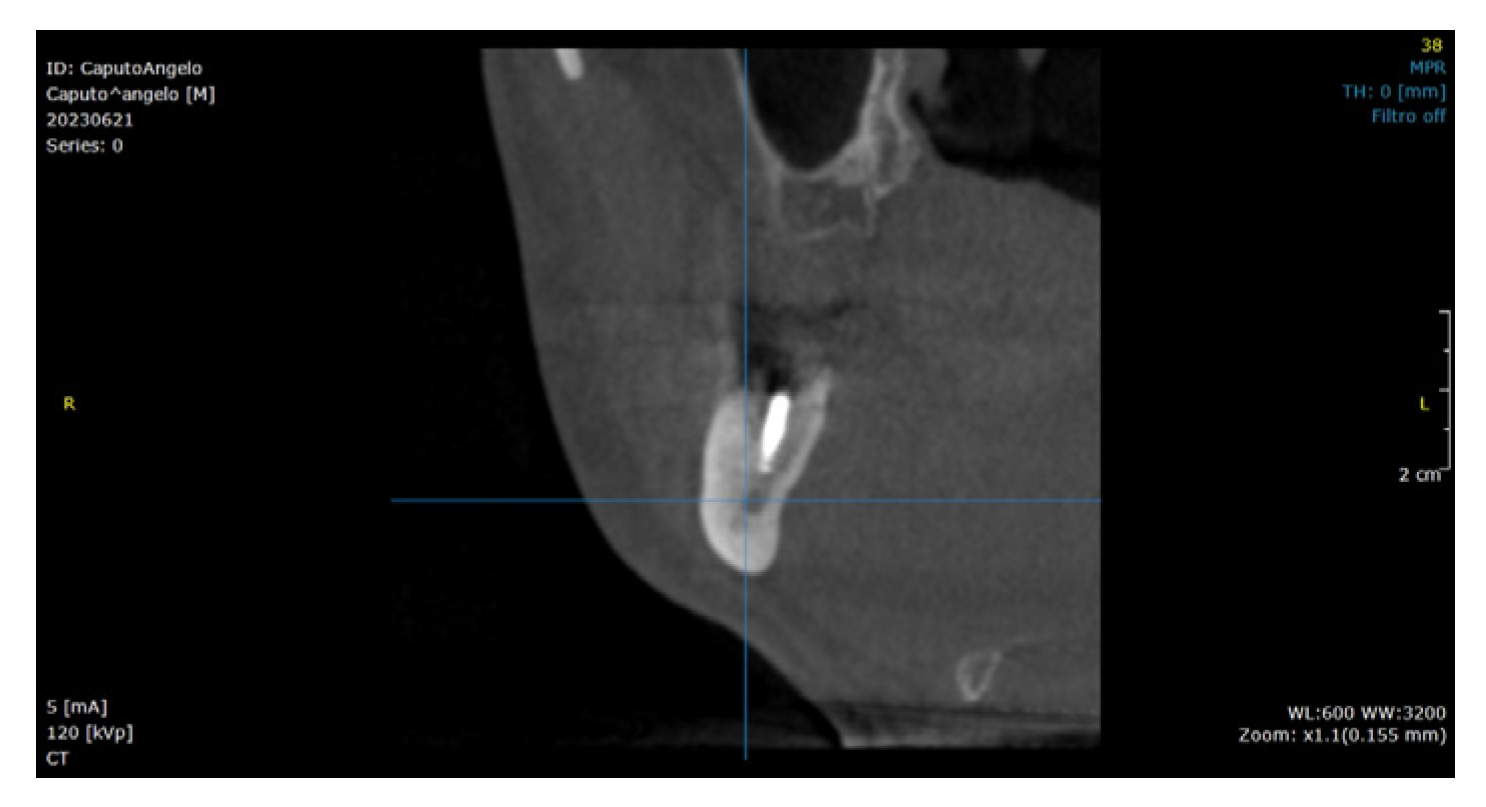

2.2. Surgical Technique